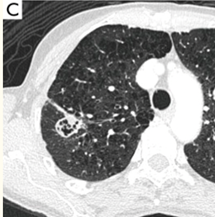

63岁男性,吸烟者,检查发现右上肺结节,既往史有COPD,随访三年结节增大,基本变实,术后病理提示右上肺浸润性腺癌 (pT1cN0M0IA3期)。